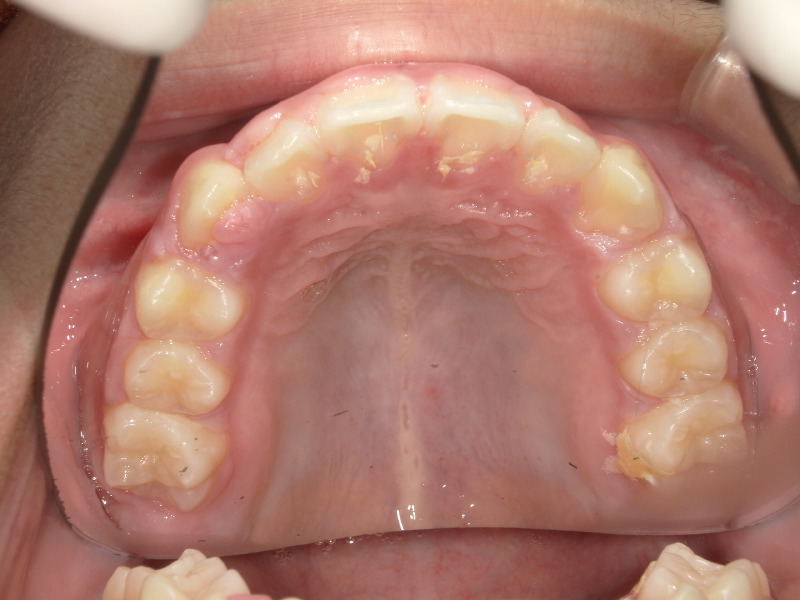

装置をつけた日と外した後、外してから3ヶ月後の写真です。

八重歯だった歯はしっかりとアーチの中に入っていて綺麗になりました。

併用の装置、マウスピースの継続で歯はかなり綺麗になりました。